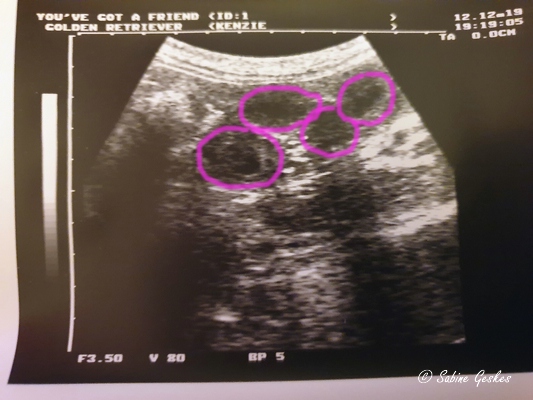

Die Spannung bis zum ersten Ultraschall ist kaum auszuhalten und natürlich haben wir schon am letzten Montag das erste Mal geschaut, ob Kenzie ein kleinen Geheimnis mit sich herumträgt. Und ja, wir haben da etwas entdeckt, was nach kleinen Fruchtanlagen aussehen könnte…. oh man, und heute (12.12.19) haben wir wieder geschaut und all unsere Hoffnungen wurden bestätigt… Wir erwarten kleine Madzies…

Jetzt müssen wir aber weiterhin alle die Däumchen drücken, dass die Kleinen auch alle bleiben und die weitere Trächtigkeit auch gut verläuft… Dann können wir in etwas mehr als 5 Wochen die Kleinen auf dieser Welt begrüßen – wir freuen uns so sehr!!!